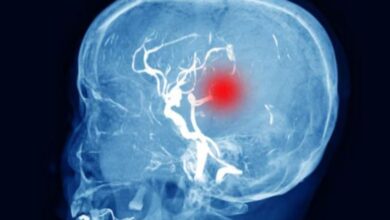

हेल्दी डाइट से शरीर ही नहीं बल्कि दिमाग को भी स्वस्थ रखा जा सकता है। विज्ञानियों का मानना है कि ऐसा करने से डिमेंशिया और अल्जाइमर्स के खतरे को भी कम किया जा सकता है।

शोधकर्ताओं ने पाया कि जिन लोगों का माइंड डाइट स्कोर उच्च था, उनकी संज्ञानात्मक गिरावट धीमी थी जब लगभग पांच साल तक उनका फालोअप किया गया। वहीं, 581 प्रतिभागियों के एक अन्य अध्ययन में पाया गया कि जिन्होंने माइंड डाइट या मेडिटेरेनियन डाइट का कम से कम एक दशक तक पालन किया, उनके दिमाग में जांच के दौरान अमाइलाइड पट्टियों के कम संकेत मिले।

अमाइलाइड पट्टियां अल्जाइमर्स रोग का एक प्रमुख लक्षण हैं। हरी पत्तेदार सब्जियों का उच्च सेवन सबसे महत्वपूर्ण डाइट घटक प्रतीत हुआ। इसके अलावा माइंड डाइट पर 13 अध्ययनों की एक प्रणालीबद्ध समीक्षा ने भी वृद्ध लोगों में माइंड डाइट के पालन और संज्ञानात्मक प्रदर्शन के बीच सकारात्मक संबंध पाया है। समीक्षा में शामिल एक पेपर ने यह भी प्रदर्शित किया कि जो लोग इस डाइट का पालन करते हैं, उनमें अल्जाइमर्स रोग का जोखिम 53 प्रतिशत तक कम हो गया। विज्ञानियों ने कहा कि यह अध्ययन अगले शोध की संभावनाओं का रास्ता खोलता है।